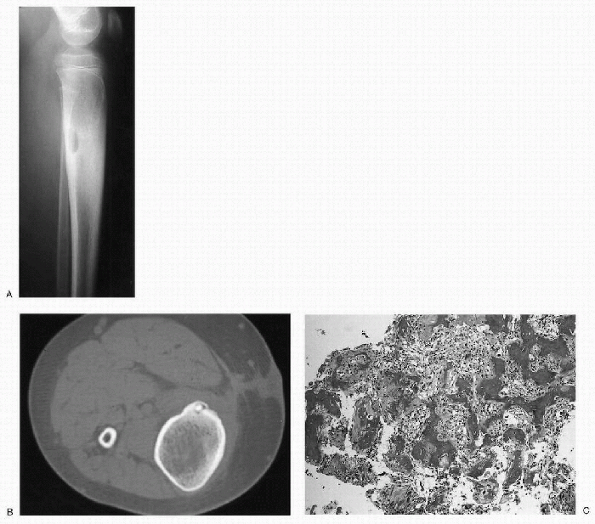

Figure 23-4 Osteoid osteoma. (A)

Lateral radiograph of the proximal leg shows a well-circumscribed lytic lesion in the posterior cortex of the proximal tibia. There is significant cortical thickening surrounding the lesion. The cortical thickening has caused widening of the tibia. (B) Axial computed tomography image demonstrates the cortical location of the lesion. There is a dense, central nidus surrounded by a lucent rim. Note the extensive cortical thickening. (C) Photomicrograph of the lesion shows a nidus composed of irregular woven bone trabeculae within a background fibroblastic stroma rich in blood vessels. |